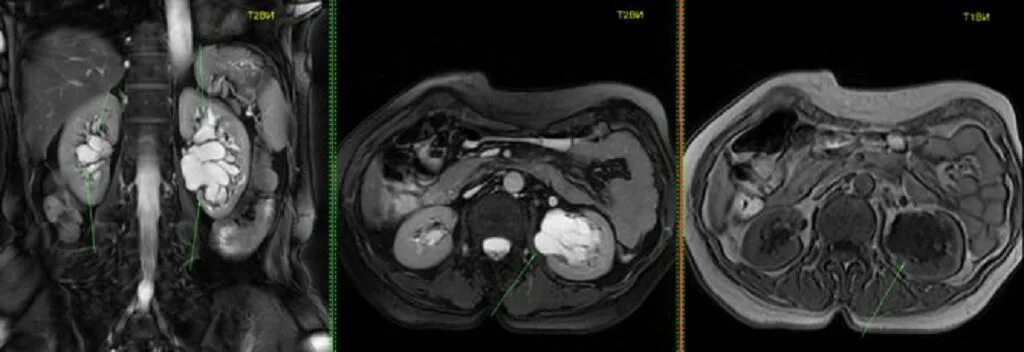

Пиелонефрит кт